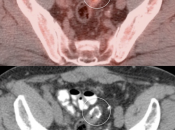

- Bladder in Inguinal Canal